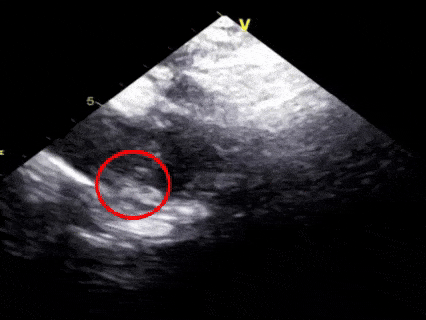

胸骨上窝主动脉弓长轴切面

一“贴”,左盘贴壁

超声下可见左盘面展开

后撤整体系统,使左盘面贴靠肺动脉一侧